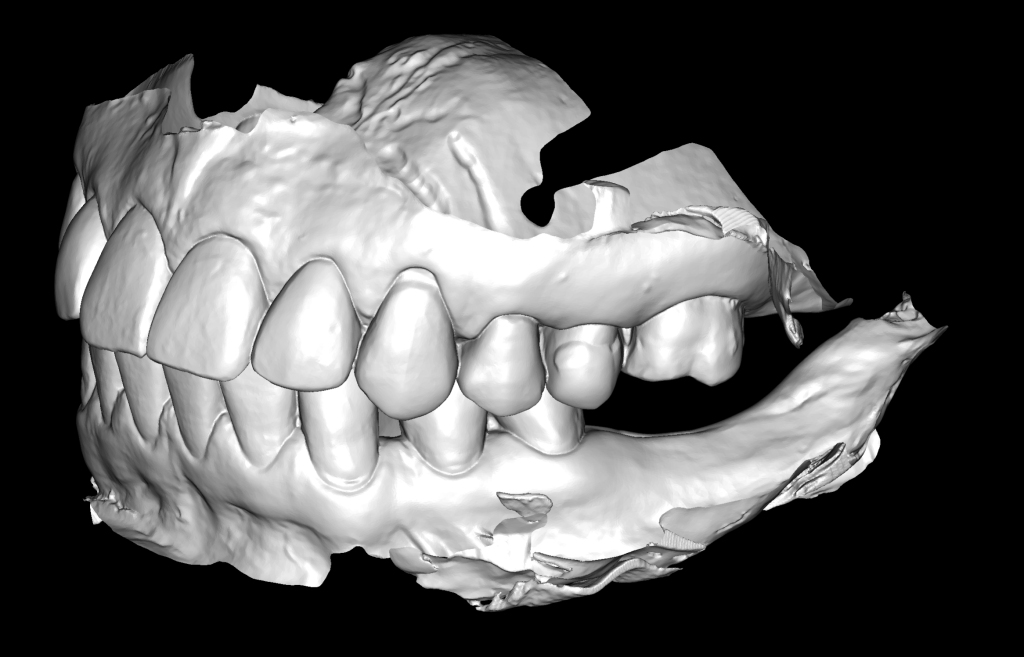

The decision has been made to perform immediate implant placement to replace teeth 24 (Universal 12) and 25 (Universal 13).The optimal position of the future implant is planned by starting with intraoral scanning and importing digital models into the Diagnocat STL module

3D reconstruction created on the basis of DICOM and an intraoral scan in the Diagnocat STL module allows you to choose the optimal size and location of the implants